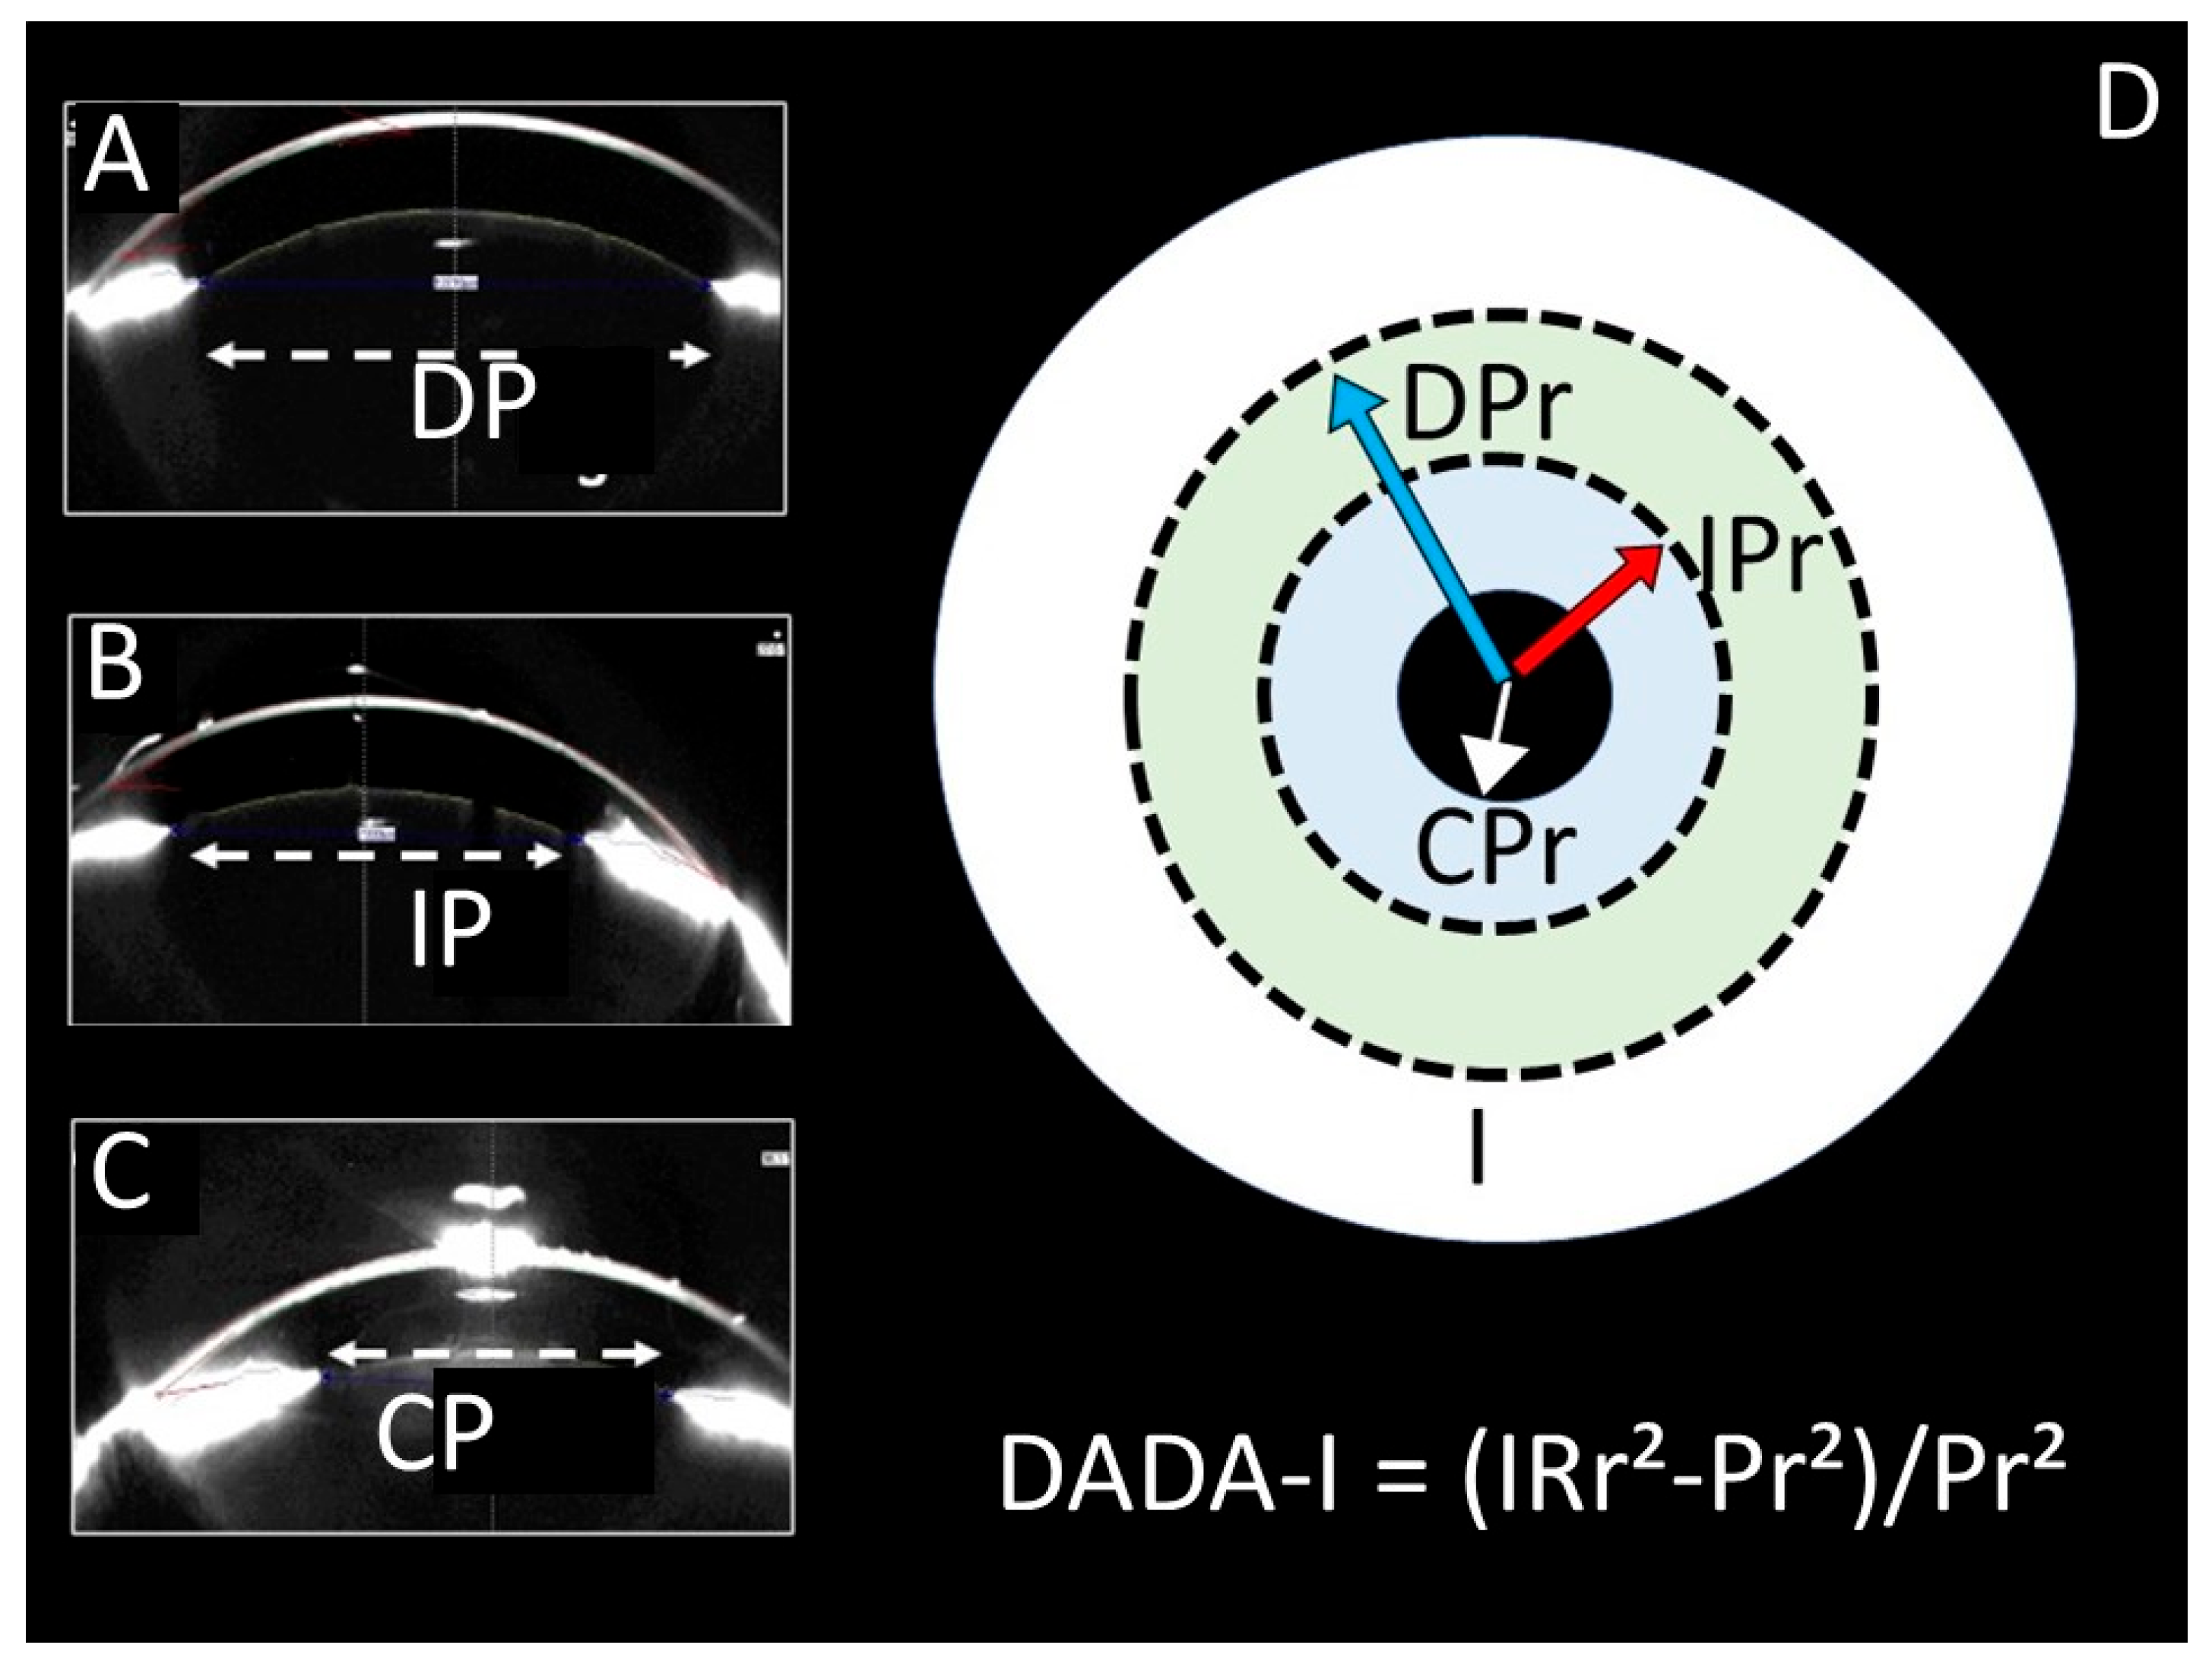

Dangerous Alarming Diameter Assessment (DADA Index) in Which the Ratio of Iris Surface/Pupil Surface Size Is More Reliable than Pupil Diameter Measurement in Comatose Patients After Subarachnoid Haemorrhage: An Experimental Rabbit Model

| DADA Index | Mean ± SS | 2.32 ± 0.43 | 1.95 ± 0.37 | 1.06 ± 0.31 | |||

| Median (Min–Max) | 2.32 (1.78–2.90) | 1.95 (1.47–2.41) | 1.04 (0.58–1.65) | 0.444 | 0.003 * | 0.008 * | |

| Dada Index | r | −0.972 ** | −0.977 ** |

| p | <0.001 | <0.001 | |

| N | 12 | 12 |